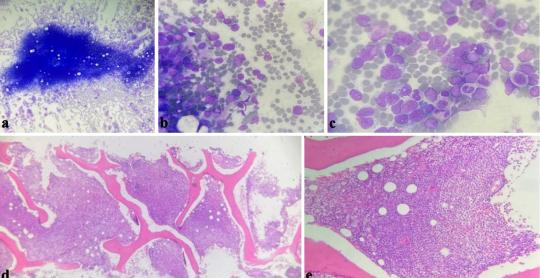

Journal of Hematology

Vol. 14, No. 5, Oct 2025, pages 267-272

By Hala Alsoukhni et al.